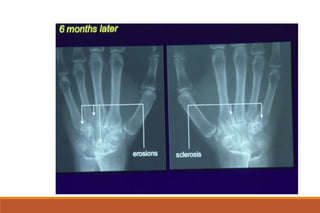

RHEUMATOID ARTHRITIS

X-rays

◦ The earliest changes occur in the wrist or feet and consist of soft

tissue swelling and juxta-articular demineralization.

◦ Later, diagnostic changes consisting of joint space narrowing and

erosions develop. The erosions are first seen at the ulnar styloid

and at the juxta-articular margin, where the bony surface is not

protected by cartilage.

◦ Diagnostic changes also occur in the cervical spine with C1-2

subluxation, but this can take several years to develop.